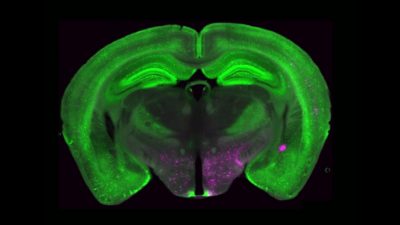

In un nuovo studio, Betley e ricercatori dell’Università di Pittsburgh e dello Scripps Research Institute hanno identificato un insieme di cellule cerebrali che svolgono un ruolo centrale nel controllo del dolore cronico. Queste cellule, note come neuroni che esprimono il recettore Y1 (Y1R), si trovano in una parte del tronco encefalico chiamata nucleo parabrachiale laterale (lPBN). Si attivano in stati di dolore di lunga durata, ma elaborano anche altri segnali legati alla fame, alla paura e alla sete. Questa sovrapposizione suggerisce che il cervello può adattare le risposte al dolore quando altre esigenze di sopravvivenza sono più urgenti.

Nell’ambito di una collaborazione con il laboratorio Taylor di Pitt, i ricercatori hanno utilizzato l’imaging del calcio per osservare i neuroni attivarsi in tempo reale in modelli preclinici di dolore acuto e cronico. Hanno scoperto che i neuroni Y1R non si limitavano a una breve attivazione in risposta al dolore acuto, ma continuavano a attivarsi in modo costante anche durante il dolore persistente, un fenomeno che i neuroscienziati chiamano “attività tonica”.

I ricercatori hanno anche caratterizzato l’identità molecolare e anatomica dei neuroni Y1R nel lPBN. Hanno scoperto che i neuroni Y1R non formavano due popolazioni anatomiche o molecolari ordinate. Questi neuroni erano invece distribuiti in molti altri tipi cellulari.